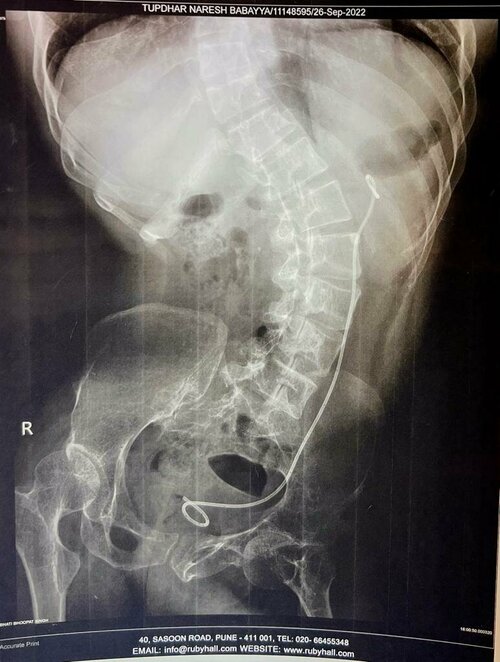

A 22 year old female was having pain in her abdomen. She visited best urologist in Pune, Dr. Bhoopat Bhati for diagnosis and treatment. Dr. Bhoopat di...